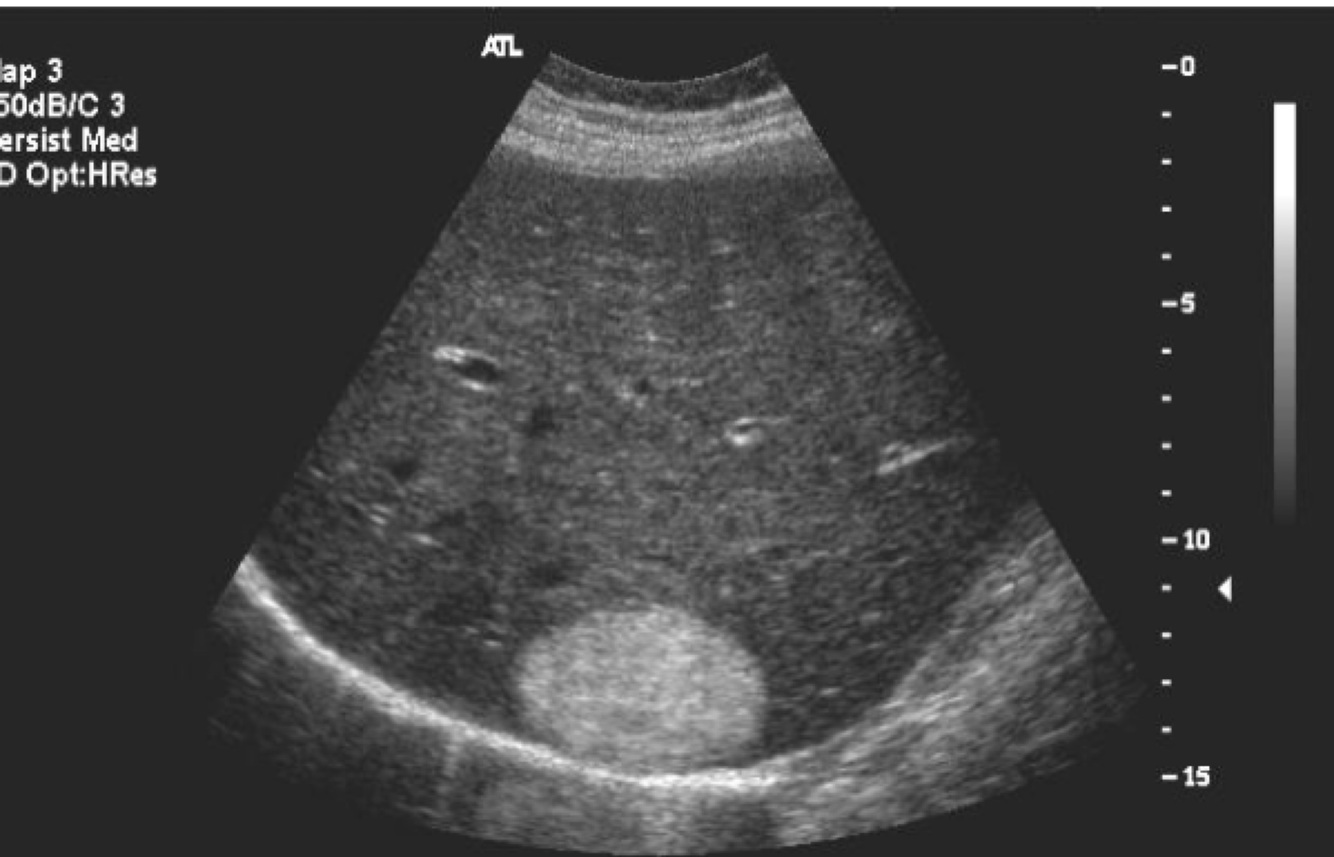

What does this image demonstrate?

Compression of adjacent organs